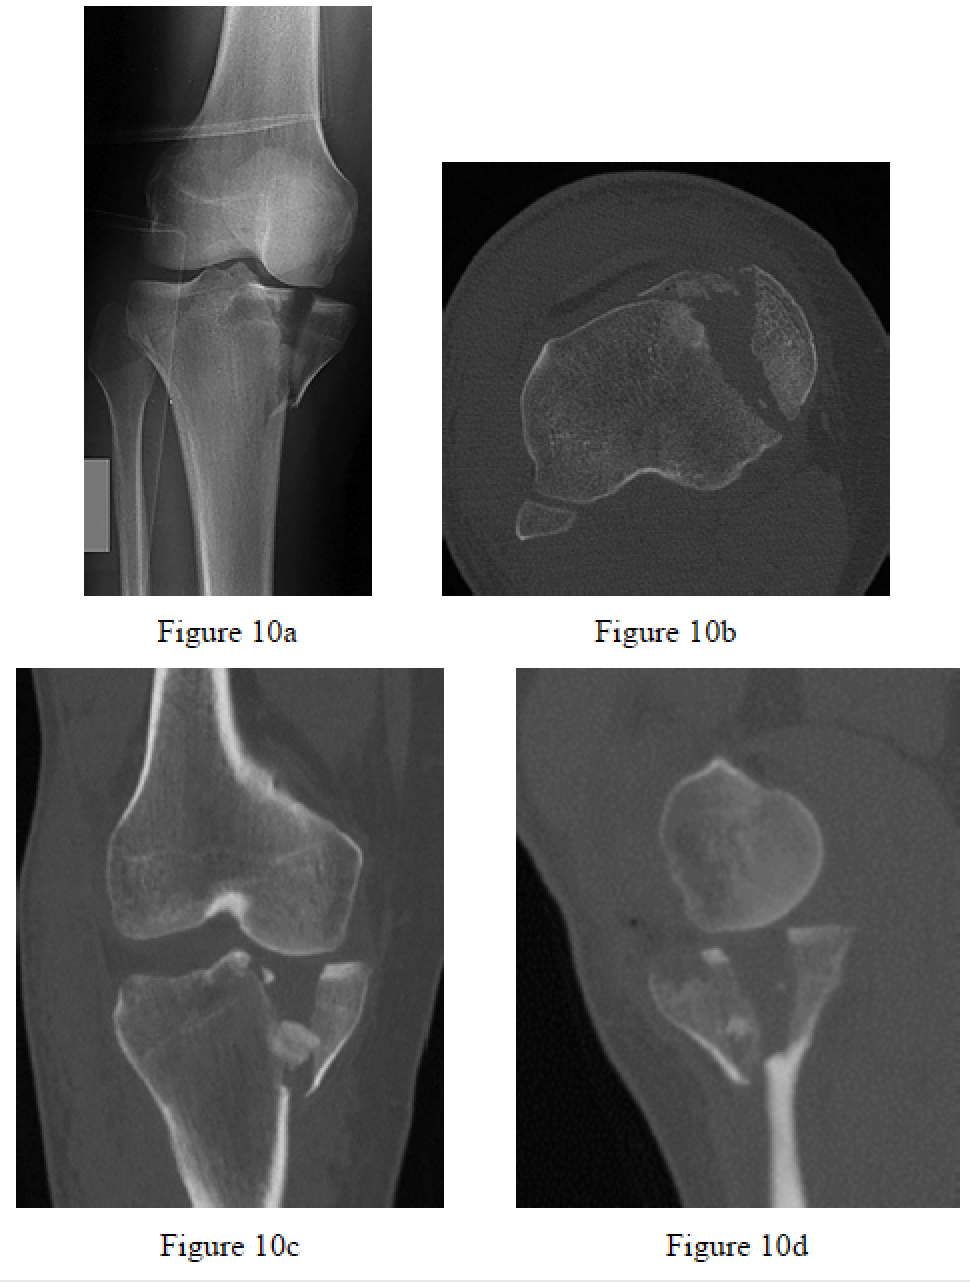

Ratcliff JR, Werner FW, Green JK, Harley BJ. Medial buttress versus lateral locked plating in a cadaver medial tibial plateau fracture model. J Orthop Trauma. 2007 Aug;21(7):444-8. PubMed PMID: 17762474.

Berkson EM, Virkus WW. High-energy tibial plateau fractures. J Am Acad Orthop Surg. 2006 Jan;14(1):20-31. Review. PubMed PMID: 16394164.